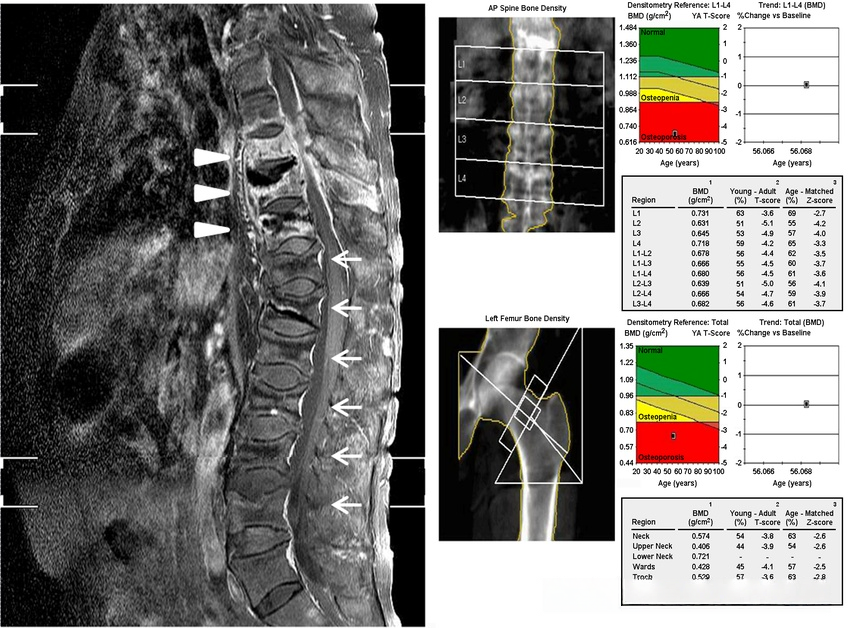

78d7497994d97e7d84a7cea36831d930.png

(A) 脊柱矢状脂肪抑制增强 T2 MRI 显示 T8、9、10 脊柱炎伴左侧椎旁和前韧带下脓肿(箭头)以及 T8 至 L5 的压缩性骨折。

(B) 腰椎和左股骨骨密度低,表明“骨质疏松症”。